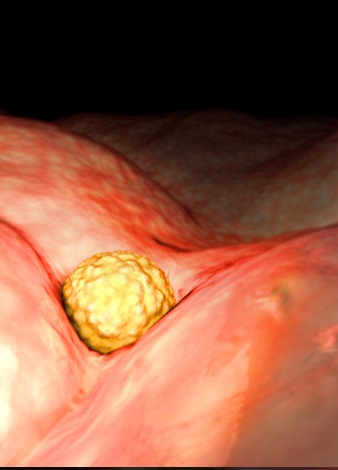

怀孕第2周胚胎图 B超图 三维图 胎儿发育 排卵通常发生在月经周期的第14天,所以,...

怀孕第2周胚胎图 B超图 三维图 胎儿发育 排卵通常发生在月经周期的第14天,所以,... -

怀孕第3周胎儿发育 这一时期,你自身可能还没有什么感觉,但在你的身体内却在进行着一场变革。...

怀孕第3周胎儿发育 这一时期,你自身可能还没有什么感觉,但在你的身体内却在进行着一场变革。... -

怀孕第3周胚胎图 B超图 三维图 胎儿发育 这一时期,你自身可能还没有什么感觉,但在你...

怀孕第3周胚胎图 B超图 三维图 胎儿发育 这一时期,你自身可能还没有什么感觉,但在你... -